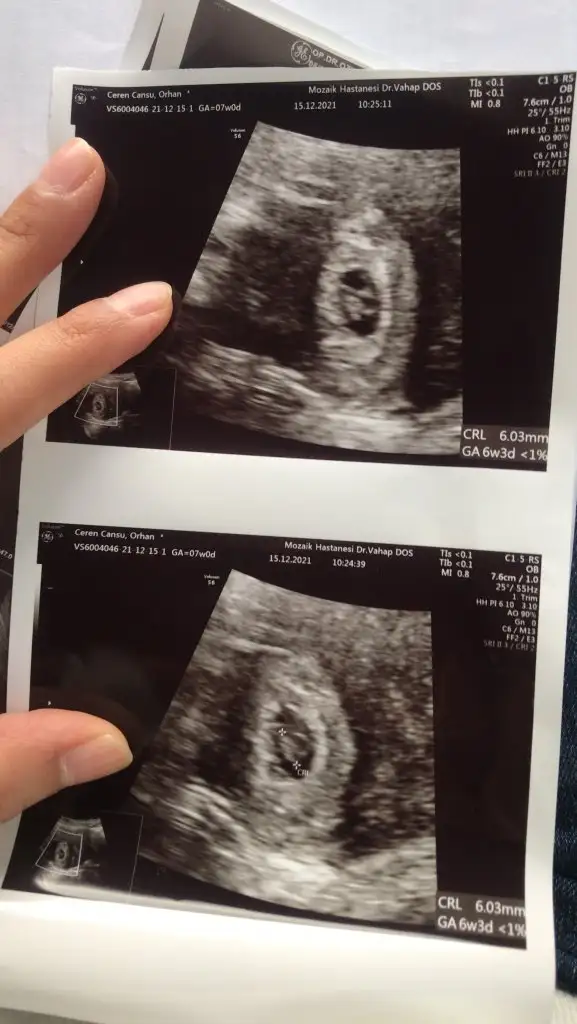

Evet canım bende bir daha 3 hafta sonra çağırdı 😅 pıt pıt pıt sesinide duyduk çok şükür 😃

Bugün bir pıtırcığın pıt pıt kalp sesini duyduk allahım isteyen herkese ama herkese hayırlı sağlıklı evlatlar nasip etsin hepimize inşlllahh 🥲🥲🥲

bendeee duydumm çok şükür Allah isteyen herkese nasip etsin saglıklı ve hayırlı evlatlar versin inşallah hepimizeeeee

Benim minnoş büyümüş mü kız erkek tahminini yeniden yap istersen bu sefer vajinal degil normal ultrason :))